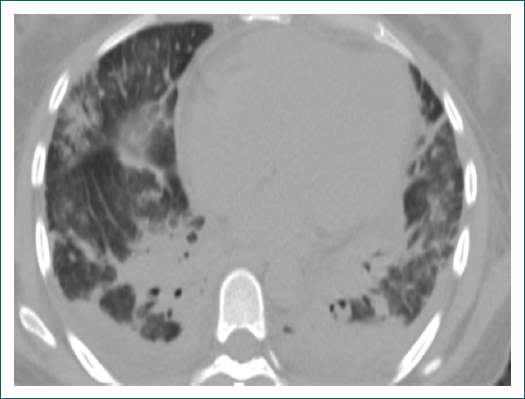

Mujer de 32 años, previamente sana, primigesta; a las 33 semanas de gestación debutó con preeclampsia grave y se le detectó óbito, por lo que se le practicó interrupción quirúrgica del embarazo. A los 5 días presentó nuevamente descontrol hipertensivo, cefalea holocraneana y amaurosis. La resonancia magnética de cráneo mostró datos de trombosis venosa del seno longitudinal superior. Durante el internamiento se inició protocolo para síndrome de anticuerpos antifosfolípido, con anticoagulante lúpico negativo; anticardiolipinas normales, IgG 4.2 GPL/ml (< 20 GLP/ml), IgM 6.49 MPL/ml (< 20 MLP/ml); anticuerpos anti-beta(2)-glucoproteína I normales: IgG 8.2 GPL/ml (< 20 GLP/ml) e IgM 11.2 MPL/ml (< 20 MLP/ml). A los 2 meses la paciente presentó úlceras orales, adenopatías cervicales, fiebre de 38.5 °C y artralgias, por lo que acudió nuevamente al hospital y presentaba neutropenia grave, linfocitopenia y anemia microcítica hipocrómica. Se inició protocolo para descartar enfermedad infecciosa, autoinmunitaria o neoplásica. Se realizó panel para virus herpes simple 1 y 2, virus de Epstein Barr y citomegalovirus, y serología para virus de las hepatitis B y C, y para virus de la inmunodeficiencia humana (VIH), los cuales fueron negativos. Factor reumatoide 10 UI/ml, crioglobulinas y anticuerpos anticitoplasma de neutrófilos negativos. Cultivo de expectoración: crecimiento de flora no patógena. Hemocultivo, urocultivo y mielocultivo sin desarrollo. Tomografía de tórax y abdomen con hepatoesplenomegalia, derrame pleural bilateral, derrame pericárdico y patrón pulmonar intersticial que evolucionó a insuficiencia respiratoria y ameritó soporte ventilatorio y vasopresor (Fig. 1). La paciente recibió tratamiento antimicrobiano empírico para neumonía atípica y factor estimulante de colonias de granulocitos y monocitos.